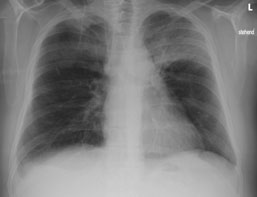

Einer Ihrer Patienten wird wegen einer Pneumonie seit 10 Tagen antibiotisch behandelt. Sie veranlassen eine Thoraxröntgen zur Verlaufskontrolle.

Hier sehen Sie das Kontrollröntgen:

Thorax pa